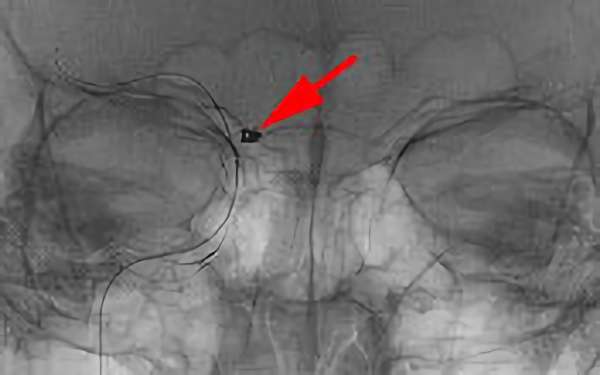

No.1631 手術中